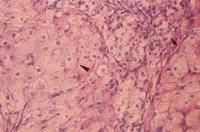

3.重度OHSS可出現肝功能不全,一些病人的肝活檢可見肝脂肪變性Kuffer細胞增生。